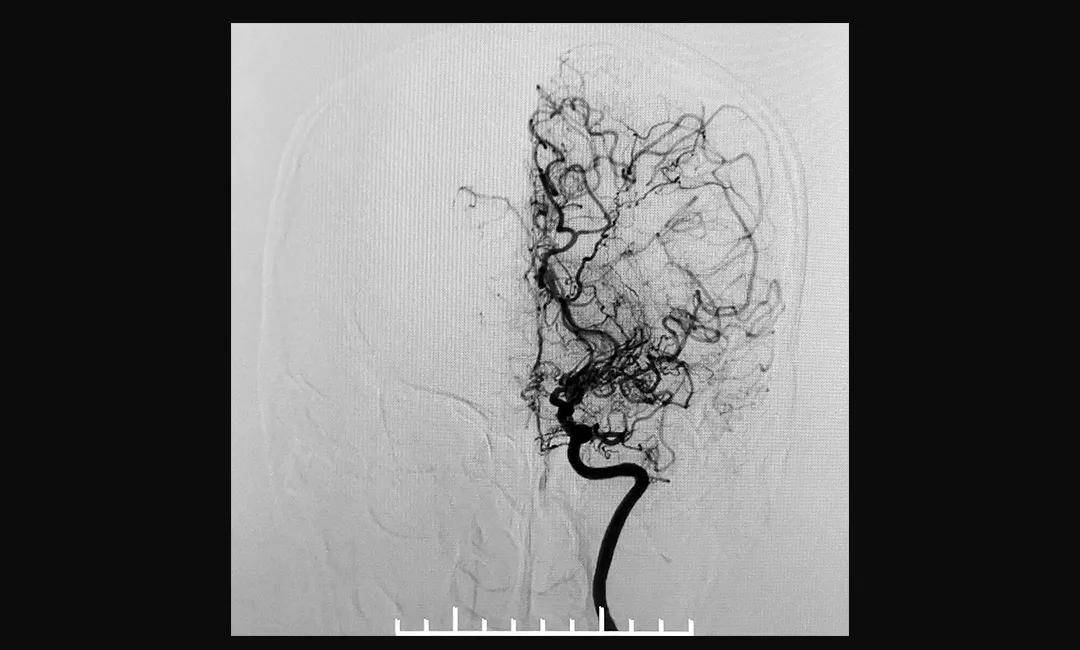

烟雾病血管造影图

烟雾病血管造影图,正常脑血管造影图

脑血管造影术(dsa)—烟雾病确诊金标准 dsa,全称叫做数字减影血管

血管在脑血管造影图像上就像袅袅升起的炊烟,故被形象的称为"烟雾病"

术前造影显示,患者双侧颈内动脉末端闭塞,颅内烟雾状血管形成

脑血管病 ,因患者脑血管造影影像类似于烟雾而著名